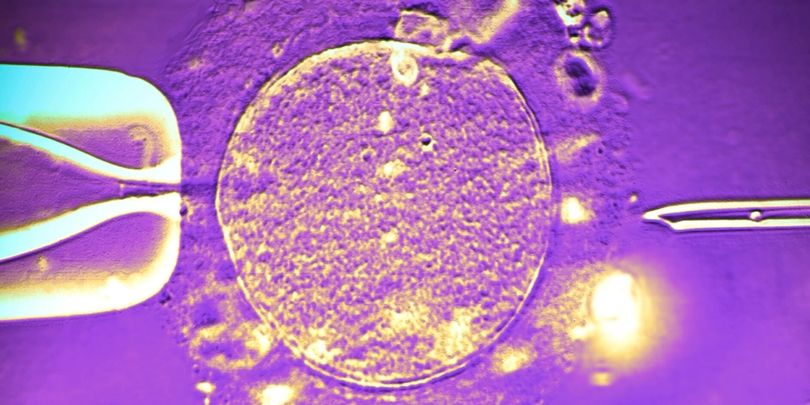

ფოტო: Science Photo Library/Canva

მედიაში გავრცელებული ინფორმაციის თანახმად, სპერმის დონორი სიმსივნის რისკის შემცველი მუტაციის მატარებელი აღმოჩნდა, თუმცა თვითონ რაიმე სიმპტომი არ აწუხებდა. სანამ ეს გახდებოდა ცნობილი, მისი სპერმის გამოყენებით მსოფლიოს მასშტაბით თითქმის 200 ბავშვი დაიბადა, რაც ნიშნავს, რომ ისინი პოტენციური საფრთხის წინაშე არიან.

2006-2022 წლებში ანონიმური ვინაობის დანიელი კაცის სპერმა 14 ქვეყნის 67 სხვადასხვა კლინიკაში გაგზავნეს, მათ შორის საქართველოშიც. მისი დახმარებით კვერცხუჯრედის განაყოფიერების შედეგად მხოლოდ დანიაში 99 ჩვილი გაჩნდა, საერთო ჯამში მათი რაოდენობა კი სულ მცირე 197 უნდა იყოს.